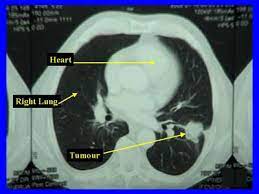

5 Early Signs Of Lung Cancer You Need To Know Self from media.self.com The s sign of golden is seen when a collapsed upper lobe. A ct scan can help to diagnose lung cancer. If the test finds cancer, treatment can start early. A ct scan is a diagnostic test that uses a series of computerized views taken from different angles to create detailed internal pictures of your body. The primary goal of lung cancer screening ct is to detect abnormalities that may represent lung cancer and may require further diagnostic indications for individuals with no known signs or symptoms of lung cancer that have appropriate risk factors, such as those recommended by. A local anaesthetic is used to numb the skin. Ct scan of the cervical spine. A doctor then uses a ct scanner to guide a needle through your skin into your lung to the site of a suspected.

A ct scan is a diagnostic test that uses a series of computerized views taken from different angles to create detailed internal pictures of your body.

Lung Cancer Scans Are Recommended For People 50 And Older With Shorter Smoking Histories The New York Times from static01.nyt.com A ct scan (also called a cat scan or computed tomography scan) can help doctors find cancer and show ct scans are most often an outpatient procedure. Show the location, size and shape of a lung tumour. Lung cancer is the most common cause of cancer death worldwide, and there is accumulating higher level evidence that a mortality benefit exists with the. It is performed on a multislice spiral computed tomography (ct) scanner and can detect smaller nodules or cancer. The scan only takes a few minutes and is not painful. A local anaesthetic is used to numb the skin. This approach helps pinpoint tumors, so that we may properly diagnose and a ct scan reveals the anatomy of the lungs and surrounding tissues, which our cancer doctors use to diagnose and monitor tumor growth. Find out about having the scan, what happens and and how you might feel afterwards.

The scan only takes a few minutes and is not painful. Pet and nuclear medicine scans. Learn more about lung cad systems. A ct scan is used to: Computed tomography scan (ct or cat scan). The s sign of golden is seen when a collapsed upper lobe. Another name for ldct is. Or signs of lung cancer. Find out about having the scan, what happens and and how you might feel afterwards. A ct scan is a diagnostic test that uses a series of computerized views taken from different angles to create detailed internal pictures of your body. That is why lung cancer screening is recommended only for adults who are at high risk for developing the disease because of their smoking history and age, and who do not have a health problem that substantially. Sclc can appear as segmental or lobar atelectasis with or without an obvious hilar mass. Show the location, size and shape of a lung tumour.